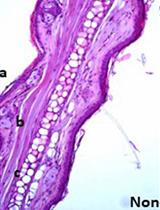

Cyst Detection in Toxoplasma gondii Infected Mice and Rats Brain

刚地弓形虫感染小鼠和大鼠脑部囊肿检测